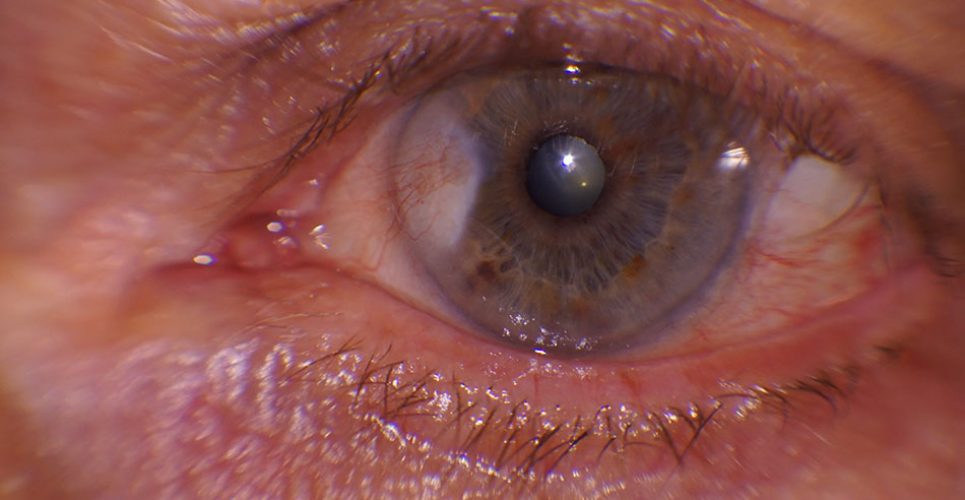

• 1ª PREMIO: “PTERIGIUM” presentado por Rocío Villena Requena